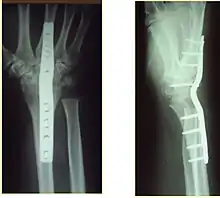

X-rays of a wrist fusion

Surgery is generally indicated for displaced or unstable fractures.[18] The techniques of surgical management include open reduction internal fixation (ORIF), external fixation, percutaneous pinning, or some combination of the above. The choice of operative treatment is often determined by the type of fracture, which can be categorized broadly into three groups: partial articular fractures, displaced articular fractures, and metaphyseal unstable extra- or minimal articular fractures.[5]

Significant advances have been made in ORIF treatments. Two newer treatments are fragment-specific fixation and fixed-angle volar plating. These attempt fixation rigid enough to allow almost immediate mobility, in an effort to minimize stiffness and improve ultimate function; no improved final outcome from early mobilization (prior to 6 weeks after surgical fixation) has been shown. Although restoration of radiocarpal alignment is thought to be of obvious importance, the exact amount of angulation, shortening, intra-articular gap/step which impact final function are not exactly known. The alignment of the DRUJ is also important, as this can be a source of a pain and loss of rotation after final healing and maximum recovery.

If the fractures are unlikely to be reduced by closed means, open reduction with internal plate fixation is preferred.[5] Although major complications (i.e. tendon injury, fracture collapse, or malunion) result in higher reoperation rates (36.5%) compared to external fixation (6%), ORIF is preferred, as this provides better stability and restoration of the volar tilt.[5][23] Following the operation, a removable splint is placed for 2 weeks, during which time patients should mobilize the wrist as tolerated.[5]